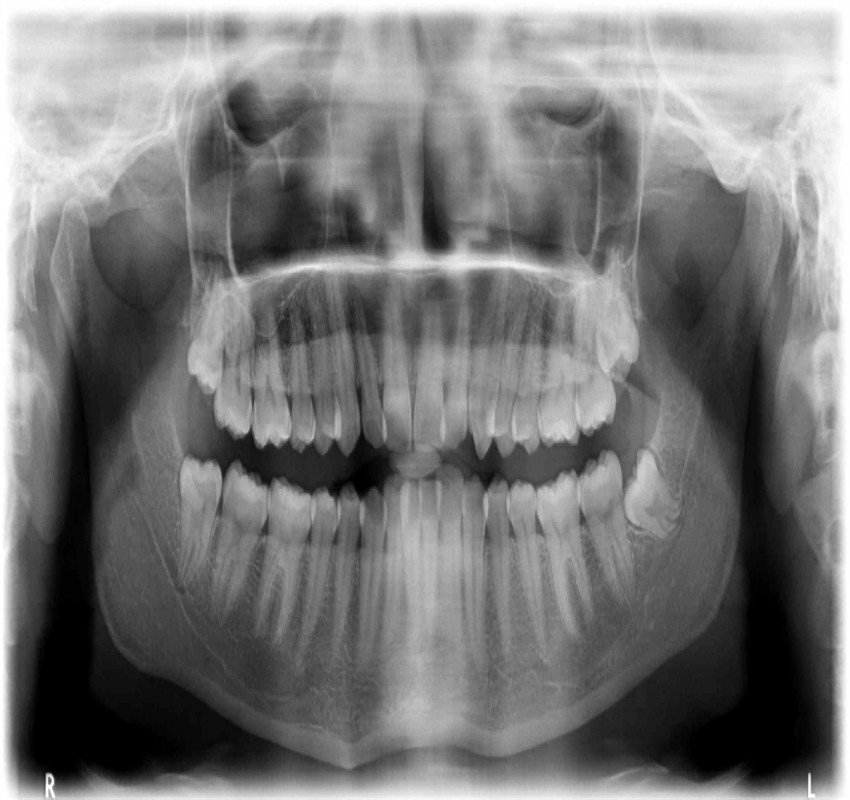

Dentistry has witnessed tremendous advances in all its branches over the past three decades. With these advances, the need for more precise diagnostic tools specially imaging methods has become mandatory. From the simple intraoral periapical x-rays, advanced imaging techniques like computed tomography, cone beam computed tomography, magnetic resonance imaging and ultrasound have also found their place in modern dentistry.

Changes from analouge to digital radiography has not only made the process simpler and faster but also made image storage and manipulation and retrieval easier. The 3- D imaging has made the complex craniofacial structures more accessible for examination.